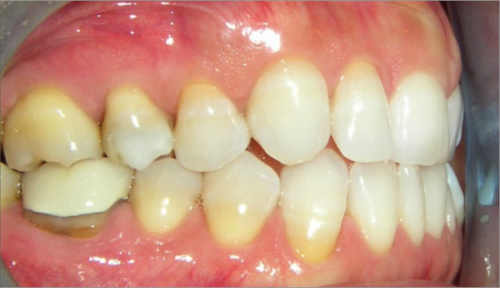

45 year old female:

Diagnosis:

- Missing upper left second bicuspid

- Lower arch crowding

- Edge to edge bite

Treatment:

- Extraction of upper & lower right second bicuspids

- Full fixed appliances

- 21 months